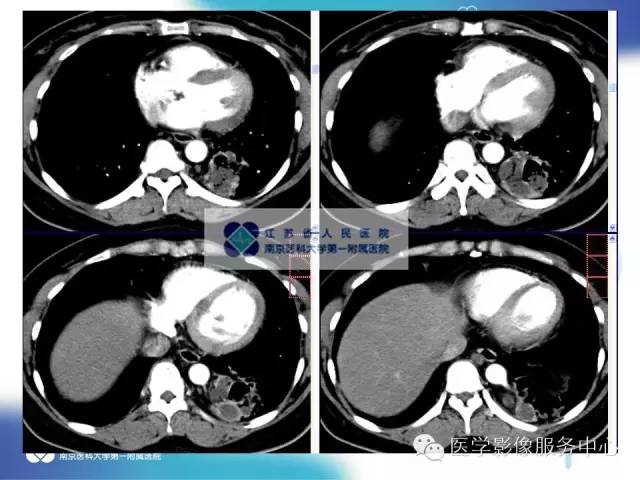

【病例】肺隔离症1例CT影像表现

女性,36岁。反复发热、咳嗽、咳痰一年。

CT:主要表现为三种类型:含有气体和液体的囊肿或软组织肿块;围绕囊肿或肿块周围的肺气肿改变;局限性肺多血管征。病变周围肺组织还可伴有支气管扩张,肺组织实变等。增强扫描病变实质可见轻度或明显不规则强化,囊性病灶可见环形强化,结合图像后处理技术( MPR、MIP、VR)多可见异常供血动脉及引流静脉,在一定程度上可以取代动脉造影。隔离肺组织供血动脉多为胸主动脉和腹主动脉,少数为隔下动脉、肋间动脉、脾动脉等。引流静脉多为肺静脉。